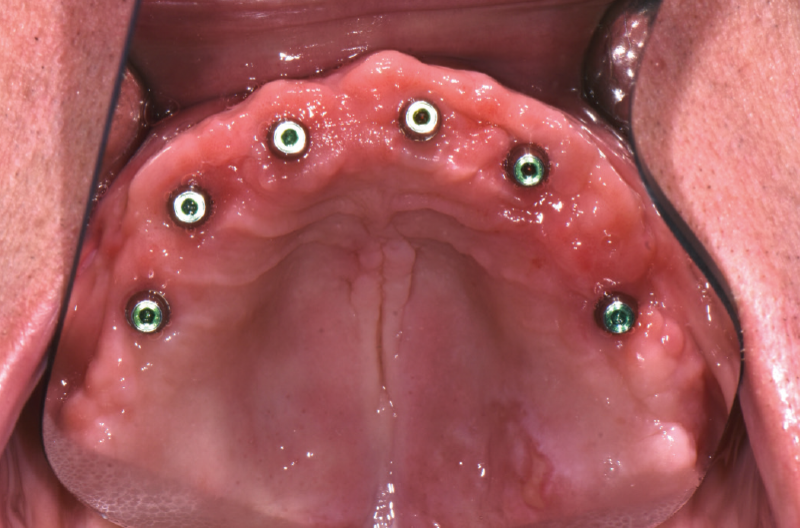

Occlusal view of MUA-Conics in the upper jaw

Fixed caps positioned onto MUA-Conics in the upper jaw by performing 1 percussion with the PEEK tip